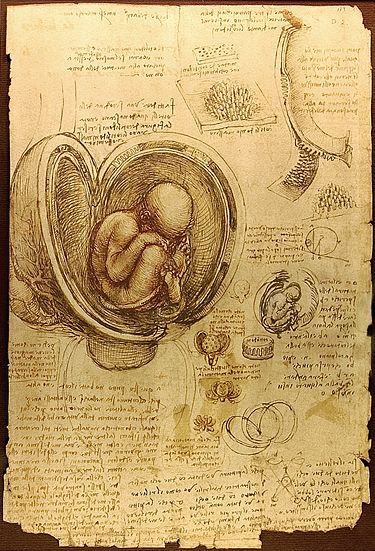

Эмбрион (др.-греч.) или зародыш — ранняя стадия развития животного и человека, начиная от оплодотворённого яйца (зиготы). Зародышевое развитие, которое происходит обычно в яйцевых оболочках или особых органах организма матери, завершается появлением способности к самостоятельному питанию и активному передвижению.

Зародышевое, или эмбриональное, развитие живого организма происходит либо в яйцевых оболочках вне организма матери, либо внутри него.

В ходе этого развития из яйцеклетки возникает многоклеточный организм, состоящий из различных органов и тканей, который способен к самостоятельному существованию. У всех животных зародышевое развитие включает оплодотворение яйца или, в случае партеногенеза, его активацию, за которым следуют стадии дробления, гаструляции, органогенеза с последующим выходом из яйцевых оболочек или рождением.

Оплодотворение происходит либо в организме матери, либо в водной среде. За оплодотворением следует дробление яйца, в ходе которого оно последовательно и многократно делится на бластомеры — сперва крупные, а затем всё более и более мелкие клетки. В итоге возникает многоклеточный организм — бластула. Цепь делений дробления создаёт предпосылки для возникновения дифференцировки, то есть различий между частями зародыша. Первичную дифференцировку обусловливает неодинаковый состав цитоплазмы клеток, возникших из разных участков яйца. Способность эмбриональных клеток к передвижениям также важна для формирования органов взрослого организма.

На стадии гаструляции обособляются зародышевые листки, и в результате возникает трёхслойная структура — эктодерма (внешний слой), энтодерма (внутренний слой), мезодерма (промежуточный слой).

Хотя на ранних стадиях развития эмбриональные клетки могут развиваться в различных направлениях, под действием ряда факторов они постепенно детерминируются (приобретают способность развиваться в лишь одном определённом направлении).

На стадии органогенеза, который обеспечивается, главным образом, разнообразными клеточными перемещениями и дифференцировкой самих клеток, происходит разделение зародышевых листков на зачатки органов и систем, в ходе которого крупные зачатки дифференцируются на более мелкие, и в результате создаётся всё более и более сложная структура целого организма. Например, из той части эктодермы, которая образует зачаток нервной системы, выделяется головной мозг. Из последнего обособляются зачатки глаз, в которых выделяется сетчатка, а в ней дифференцируются специализированные зрительные клетки —палочки и колбочки. Зародышевое развитие различных групп животных проходит неодинаково: у зародышей рыб образуется большой желточный мешок, птицам свойственны желточный мешок и особые органы — аллантоис и амнион, а млекопитающим, кроме того, ещё трофобласт и плацента.